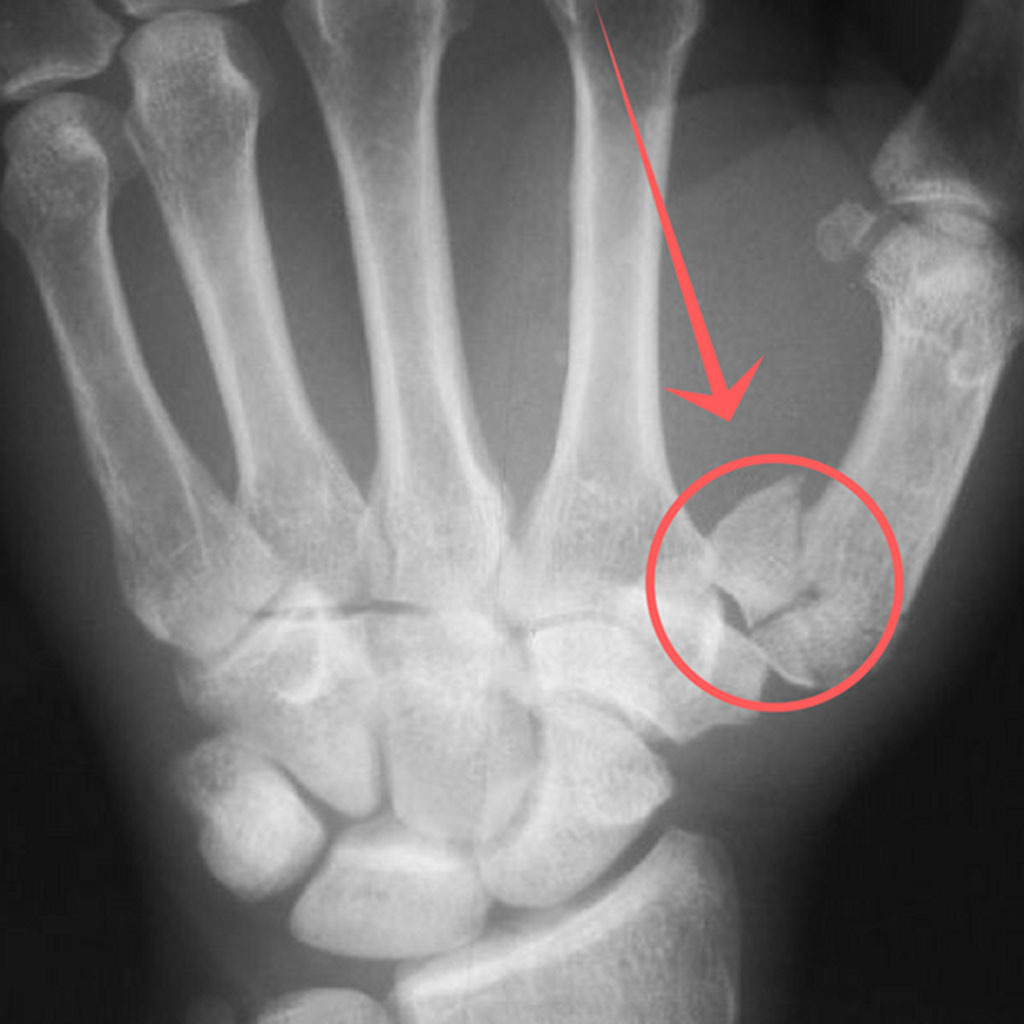

진료비와 검사비

- X-ray 촬영: 기본적으로 뼈 상태를 확인하기 위해 X-ray 촬영이 이루어지며, 병원에 따라 2~5만 원 내외의 비용이 들 수 있습니다.